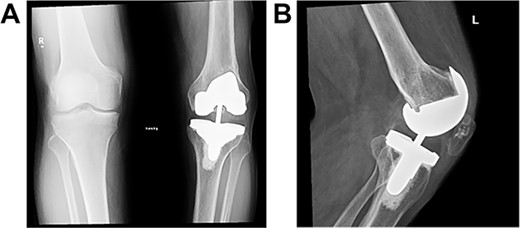

Post-operative plain radiographs from follow-up visits; (A) 3-month post-operative AP radiograph showing implant in place with a lateral gap sized to be 3.2 cm; (B) 3-month post-operative lateral radiograph of the knee showing implant in a satisfactory position.

Post-operative plain radiographs at 2-year follow-up visit; (A) 2-year post-operative AP radiograph showing implant in place with decreased lateral gap sized to be 1.57; (B) 2-year post-operative lateral radiograph of the knee showing implant in a satisfactory position.